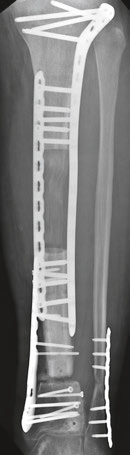

п▓п╬я┌ я█я┌п╦ п╨п╟я─я┌п╦п╫п╨п╦ п╬я│п╬п╠п╣п╫п╫п╬ п╥п╟я├п╣п©п╦п╩п╦.

> https://yadi.sk/i/3vDiLZUc3S8fbq